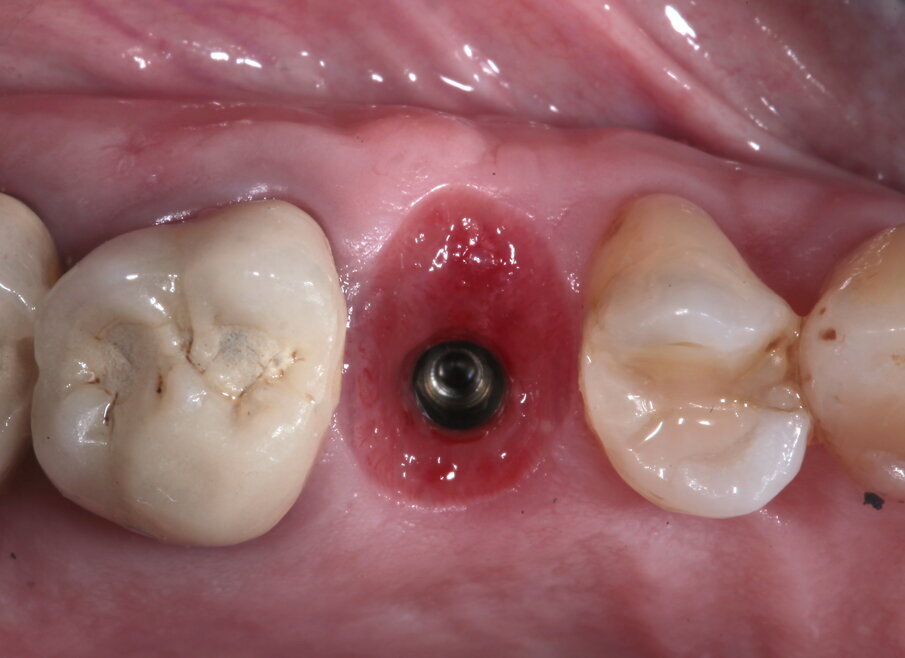

Viene disegnato un roll flap, posizionato l’impianto tramite una mascherina di guida per la fresa pilota ottenuta tramite stampa 3D, inserita una vite di guarigione transmucosa e suturato il lembo. Dalle immagini intraoperatorie si può notare come la scelta di materiale a rapido riassorbimento abbia permesso l’ottenimento di un osso vitale, sanguinante e con la quasi totale assenza di particelle di biomateriale ancora presenti. L’imprecisione nella sutura della porzione distale del lembo genererà uno spessore maggiorato del connettivo in quella zona, che avrà come effetto un piccolo inestetismo che tuttavia la paziente non nota e che non intende correggere (Figg. 14-17). Al termine dei 4 mesi necessari al completamento del processo di osteointegrazione, viene inserito un provvisorio avvitato con il quale inizia il condizionamento dei tessuti perimplantari.